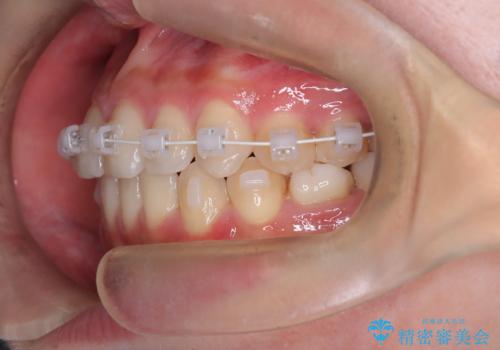

- 矯正装置

- 審美装置

インビザラインを希望されておりましたが、20時間もつけることができなかったためワイヤー矯正にて叢生の改善を行っています。

右上の側切歯(前から2番目の歯)が90度程度ねじれている状態でしたが、1月に1回のワイヤー交換できれいに並ぶことができ満足いただけました。